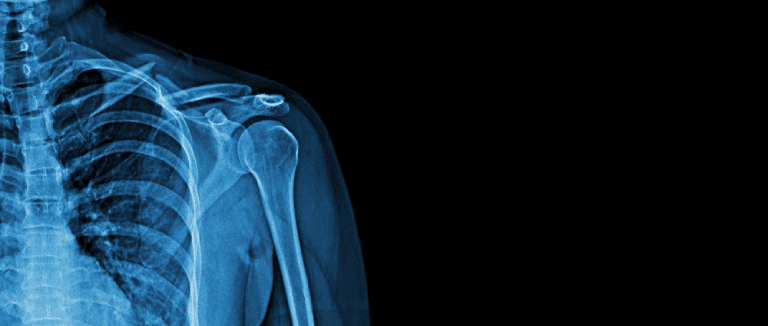

Total Shoulder Arthroplasty (TSA)

TSA is used to treat serious rotator cuff injuries or severe shoulder arthritis. This treatment replaces the left or right shoulder's injured ball-and-socket joint with artificial parts.